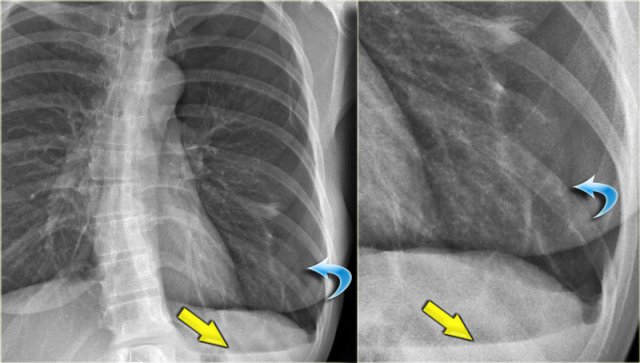

Silhouette sign (3)

Here a consolidation which is located in the left lower lobe (yellow arrow).

Notice that there is a normal silhouette of the left heart border (blue arrow).

The absence of a silhouette sign tells us that the pathology is located in the left lower lobe and not in the lingula.